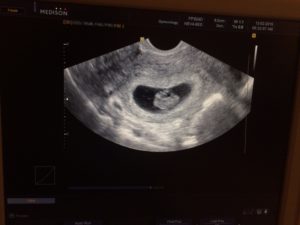

Узи 8 недель беременности

Узи 8 недель беременности: при беременности 8 недель уже можно различить ножки, ручки, просматривается позвоночник. Сердце занимает около 50% грудной клетки и бьется с частотой 160 уд/мин.